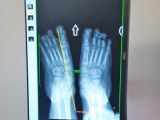

Krzyś cierpi na czterokończynowe dziecięce porażenie mózgowe wraz z koślawością szpotawą stóp. Potrzebuje pilnie kosztownej operacji (150 tys. zł) żeby móc stanąć na nogi. Gorąco apelujemy o pomoc dla niego.

Każdego dnia mierzę się z trudną codziennością, ale nie mogę się poddać. Wiem, że jeśli odpuszczę, jeśli się poddam, stracimy wszystko co wypracowaliśmy z wielkim wysiłkiem dzięki naszej determinacji i pomocy dobrych ludzi. Dzisiaj Krzyś ma 7 lat. Nie mówi, komunikuję się tylko poprzez gesty. Pierwsze kroczki za rękę postawił w sierpniu 2021 roku, dziś przejdzie parę kroków sam ale nóżki które są krzywe nie pozwalają mu na więcej… Rezonans magnetyczny, wykazał w główce Krzysia torbiele, przez co zaczął tracić równowagę. Nawiedzają mnie straszne myśli, które odsuwam od siebie.

Jesteśmy już po kilku konsultacjach w Instytucie Dr Paley'a w Warszawie. Krzyś wymaga pilnej operacji obu nóżek, operacja będzie polegała m.in.: na usunięciu kości pięty i wydłużeniu jej, umieszczeniu implantów, zabieg ścięgien Achillesa. Chcemy wierzyć, że koślawość szpotawa stóp mojego synka będzie wkrótce tylko przykrym wspomnieniem, że Krzyś zapomni jak bolało i wszystko będzie dobrze.